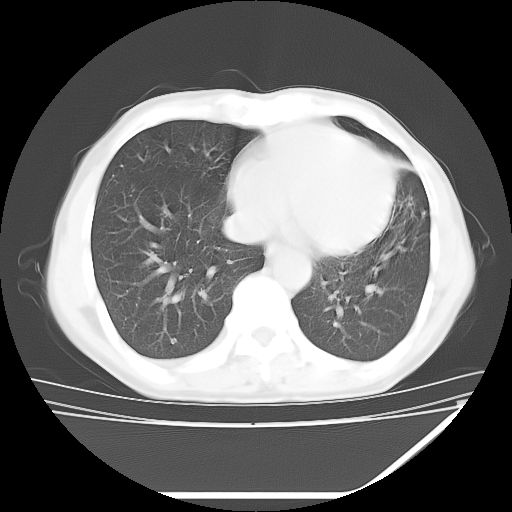

男,59岁,“结核性胸膜炎”30余年,胸部经常疼痛,多次x检查提示“肺部”炎症。腹部疼痛5日,b超提示:“肝内短管结石,余显示不清,建议进一步检查。”

两肺结核并右侧胸腔积液;脾脏、腹腔及腹膜后淋巴结结核[陈旧性];肝内胆管结石

胸部腹部都是结核(双肺。纵隔淋巴结,肝脏,脾脏,肠系膜)